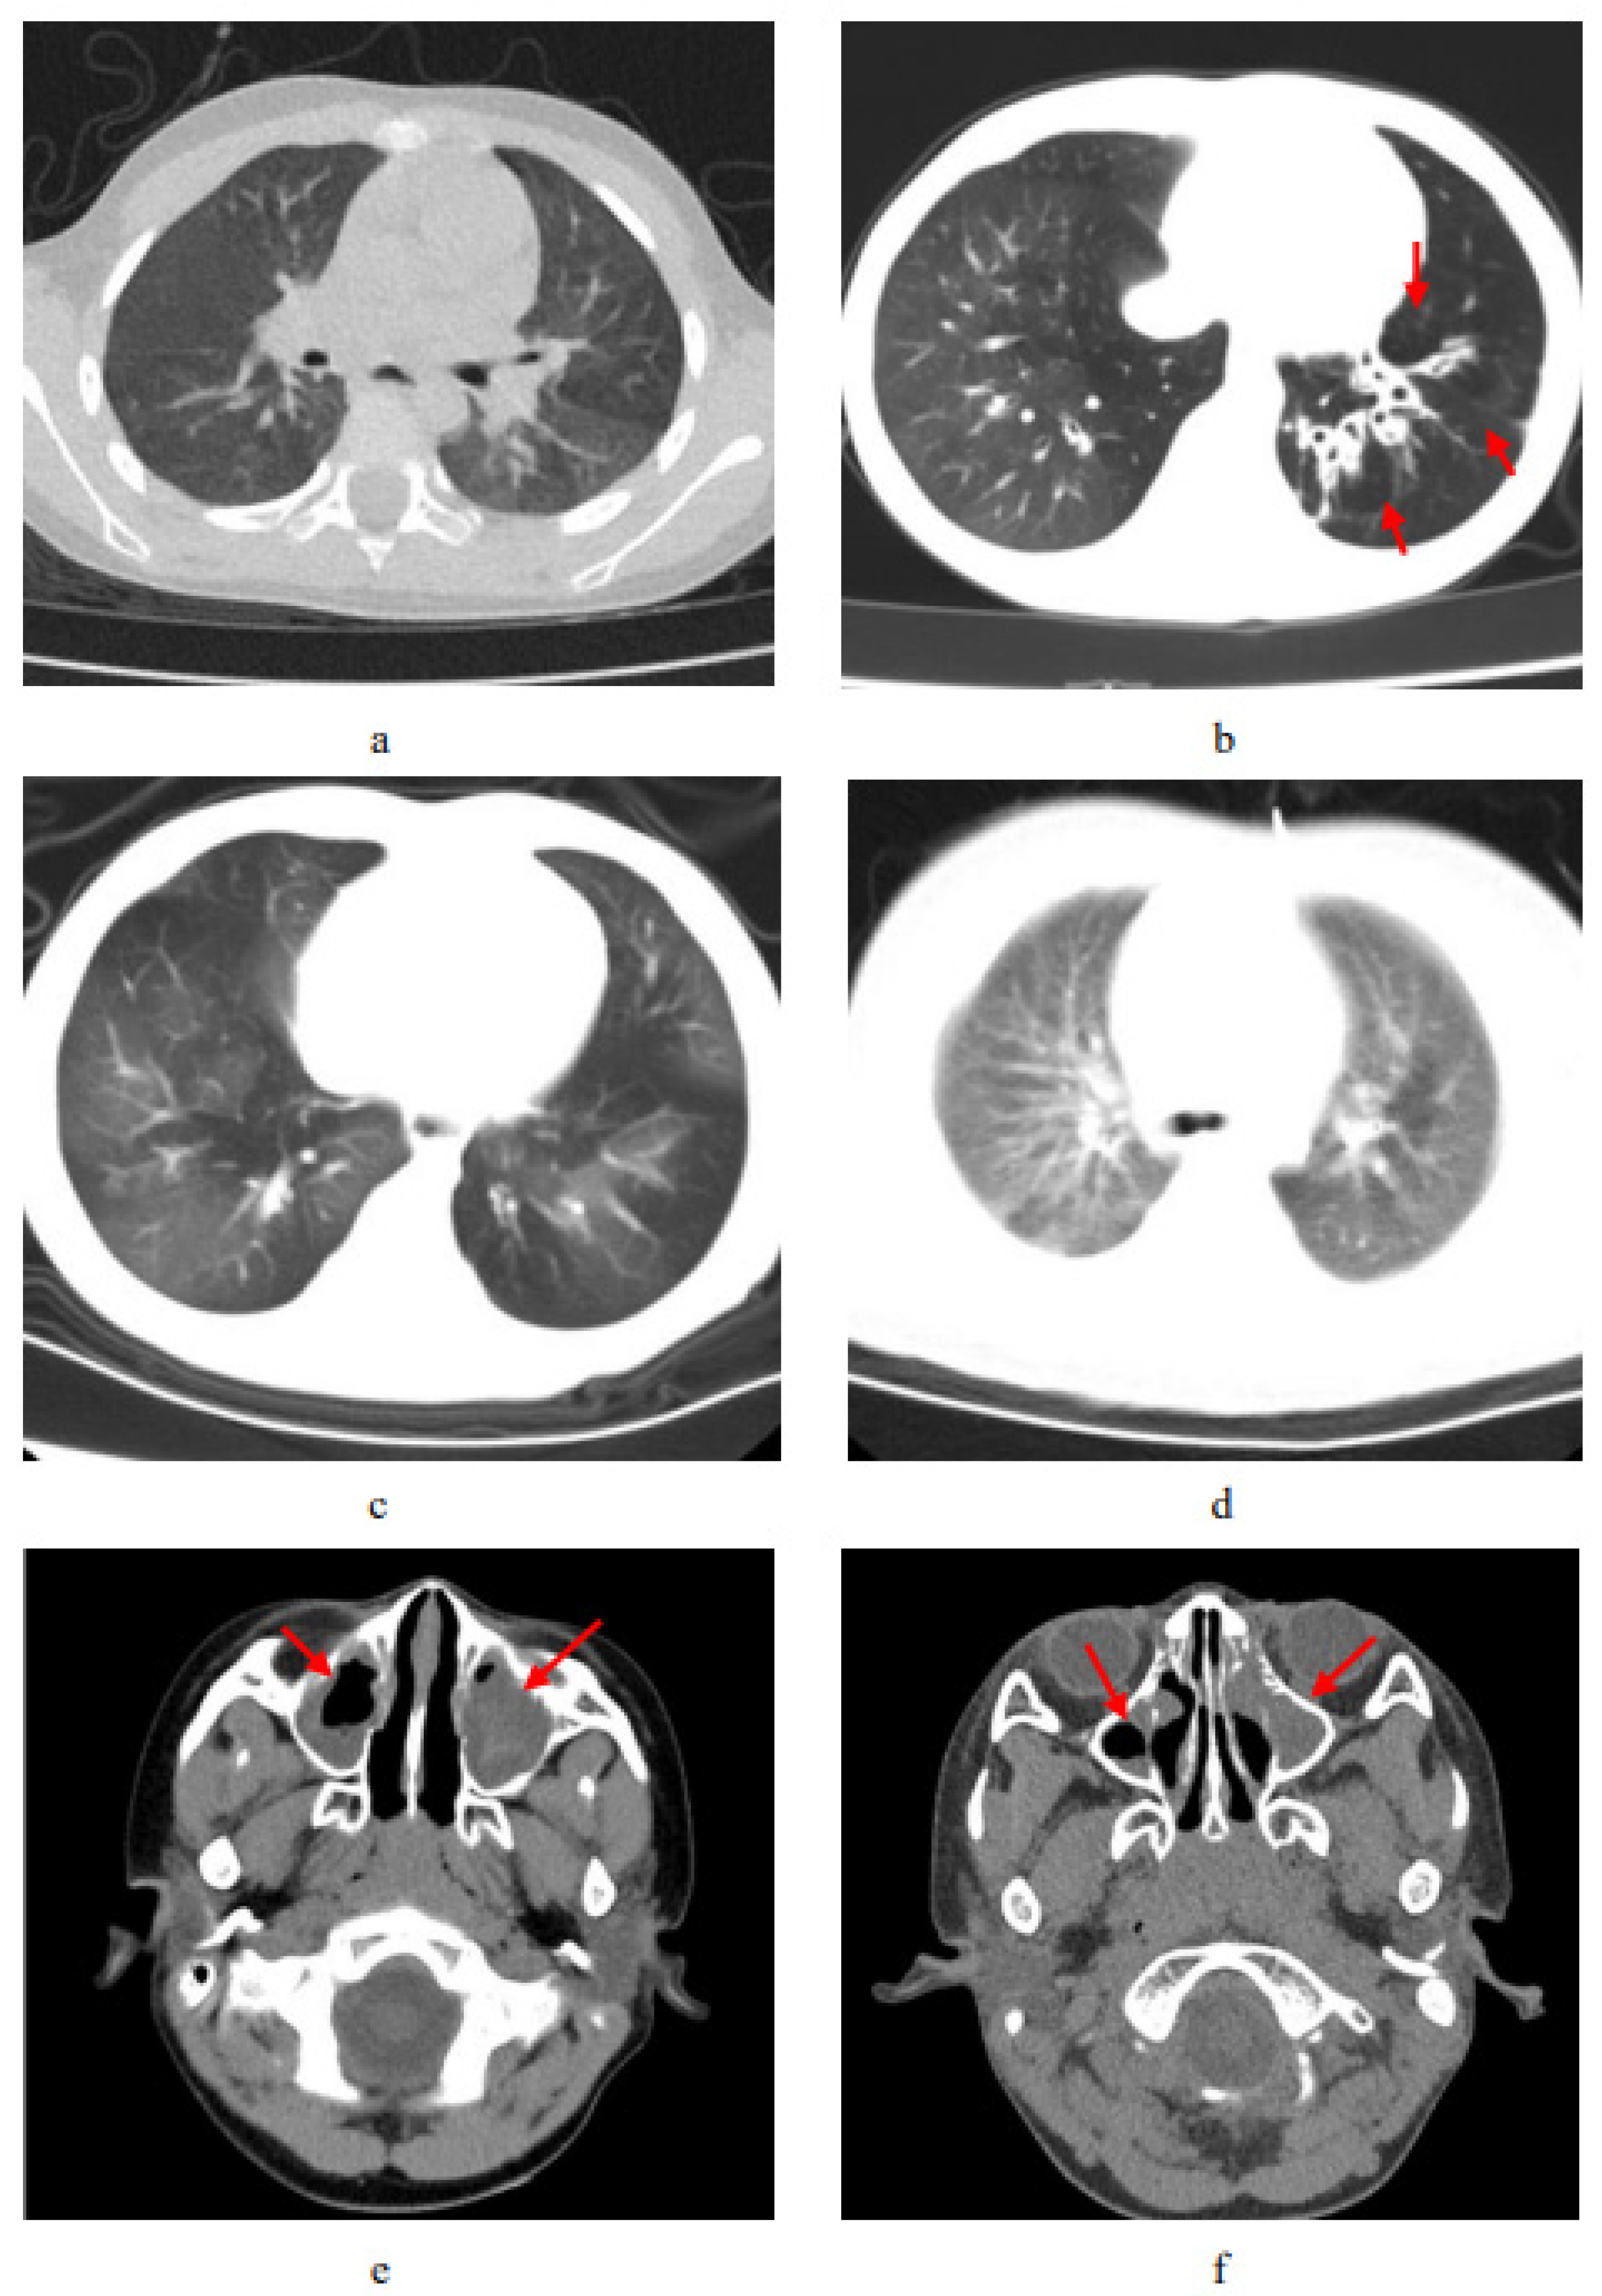

3.4. Imaging Features of Chest and Nasopharynx